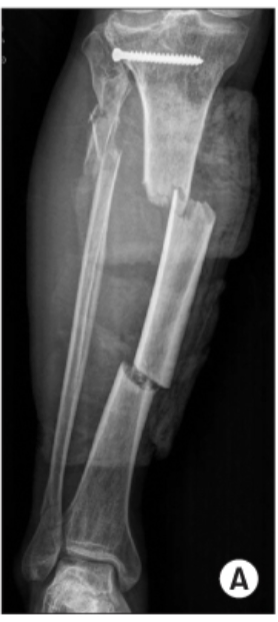

Spiral Fractures

Fracture line is

rotated around the

longitudinal axis of

the bone

The length is at

least twice as long

as the width of the

bone involved